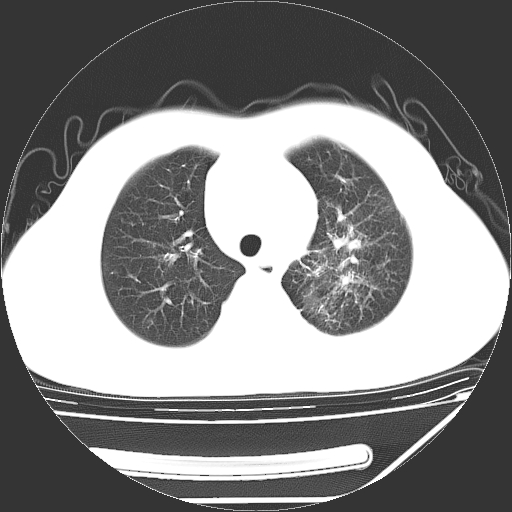

男,13岁,咳嗽、咳痰伴发热一周。

中上纵隔见多枚淋巴结肿大,部分相互融合成团片,左肺门增大,上叶支气管变窄,肺内多处斑片状 索条状及棉絮状致密影。临床“男,13岁,咳嗽、咳痰伴发热一周。”首先考虑:原发综合征!不除外淋巴瘤可能!

纵隔多发肿大淋巴结,部份有融合改变。双肺血管气管束增厚,以肺门为中心向外周散发,以左肺下叶为明显。考虑淋巴瘤可能性大。不除外原发综合征。

中上纵隔见多枚淋巴结肿大,部分相互融合成团片,左肺门增大,上叶支气管变窄,左肺支气管血管束增粗,可见磨玻璃样影。临床“男,13岁,咳嗽、咳痰伴发热一周。”首先考虑:淋巴瘤可能性大!

单纯看片子感觉左侧肺通气不畅,而不像肺内病变引起的纵隔病变。而且纵隔及左肺门都有淋巴结增大。首先还是考虑一下结节病,不排除淋巴瘤!!!